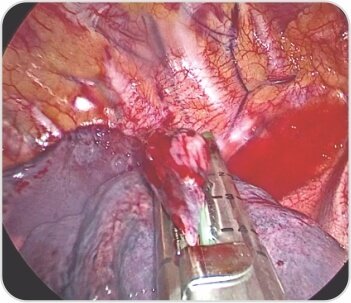

Right upper lobe apical segment bullae

Bullectomy with endostaplers